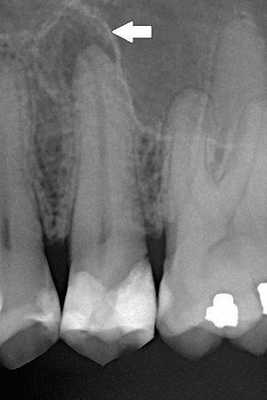

На прицельной рентгенограмме: коронковая часть 13 зуба отсутствует, в области верхушки корня определяется деструкция костной ткани с чёткими ровными контурами размером ~ 0,3*0,5 см. Деструктивные изменения в периапикальной области соседних зубов не визуализируются.

Данные рентгенологического исследования: на внутриротовой контактной рентгенограмме удовлетворительного качества зуба 4.7 в области коронки на окклюзионной поверхности определяется очаг затемнения, соответствующий пломбе неудовлетворительного качества, а также очаг просветления с нечеткими контурами, соответствующий глубокой кариозной полости, сообщающийся с полостью зуба. Коронковая часть полости зуба и корневые каналы свободны от пломбировочного материала, корневые каналы прослеживаются на всем протяжении. Периодонтальная щель сохранена. Структура костной ткани не изменена. Компактная пластинка вершин межальвеолярных перегородок сохранена.

На внутриротовой контактной рентгенограмме удовлетворительного качества зуба 4.7 в области коронки на окклюзионной поверхности определяется очаг затемнения, соответствующий временной пломбе. В корневых каналах прослеживается однородная тень контрастного пломбировочного материала на всем протяжении каждого канала до физиологических верхушек. В периапикальных тканях изменений не выявлено. Компактная пластинка вершин межальвеолярных перегородок сохранена.